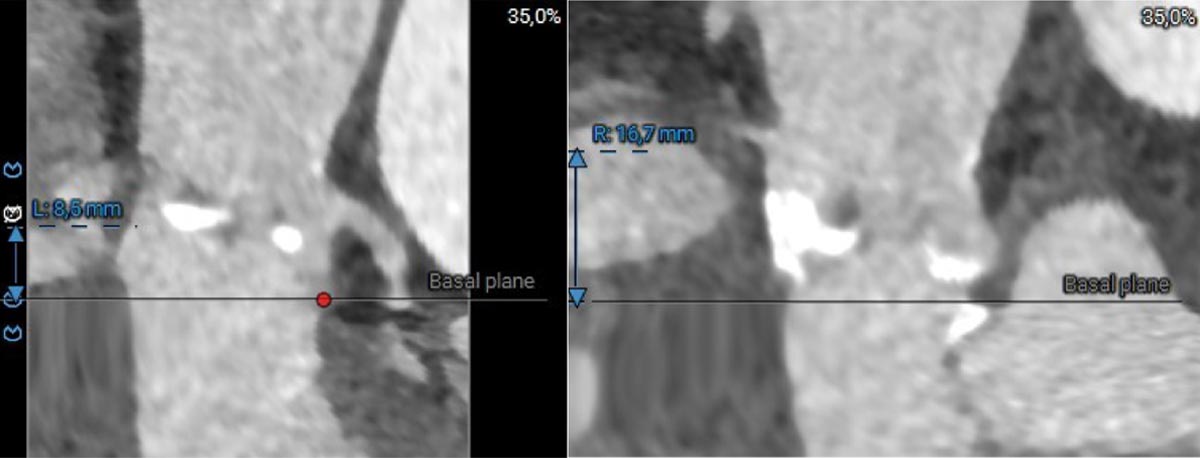

Die Planungs-Computertomographie (Abbildung 2-6) zeigte eine stark verkalkte Aortenklappe (Agatston-Score 3.398, Kalziumvolumen 2.627) mit leicht asymmetrischen Taschenklappen, wobei die nichtkoronare Tasche die größte war. Der linksventrikuläre Ausflusstrakt (LVOT) war verkalkt, beginnend auf Annulusebene bis 5,1 mm in den LVOT unterhalb der linkscoronaren Tasche reichend. Die Aortenwurzeldiameter waren niedrig: Anulus (aus dem Perimeter abgeleiteter Durchmesser 22,3 mm), linker ventrikulärer Ausflusstrakt (LVOT) bei 4 mm (19,9 mm), Sinus valsalva (SOV) (links 24,4 mm, rechts 25,3 mm, noncoronar 27,3 mm) und sinutubulärer Übergang (STJ) (24,0 mm). Darüber hinaus zeigte sich ein geringer Abstand des Ostiums der linken Koronararterie zum Annulus (8,6 mm) und eine horizontale Aorta (74°). Die Aorta, die Iliaca und die Femoralarterien waren für einen transfemoralen Zugang geeignet.

Abbildung 4: Computertomographie - Koronarabstand

- Niedriger Koronarabstand (LCA 8,6 mm) mit kleinem Diameter in SOV und STJ, daher potenzielles Risiko einer periinterventionellen Koronarobstruktion

Die kontrastmittelverstärkte Computertomographie zeigte spezifische anatomische Herausforderungen: a) trikuspide Aortenklappe mit massiver Verkalkung (Agaston-Score 3,398), b) Verkalkungen des linkskoronren Annulus bis in den linksventrikulären Ausflusstrakt (LVOT) reichend, c) kleiner Aortenklappenannulus mit einem Durchmesser von 22 mm und schmalem 19 mm LVOT, d) kleine Aortenwurzeldimensionen, d) 8.6 mm Abstand des LCA-Ostiums zur Annulusebene und e) eine 74° horizontale Aorta.